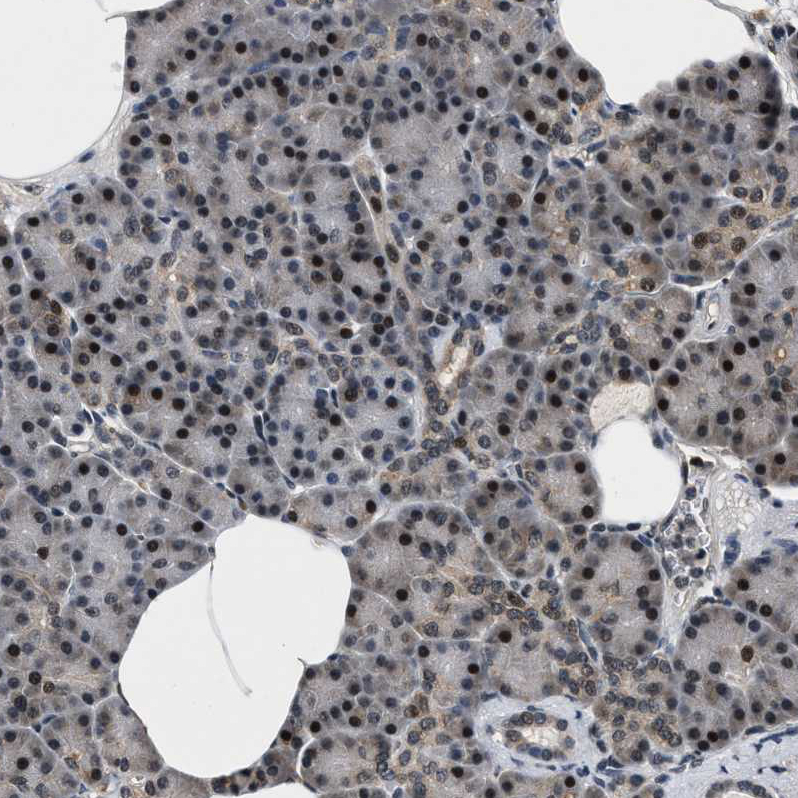

Immunohistochemical staining of human cerebellum shows moderate nuclear positivity in Purkinje cells.